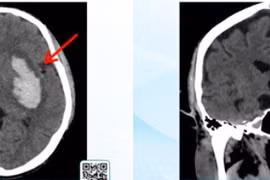

Hành trình cấp cứu xuất huyết não từ hôn mê đến hồi sinh

Ê-kíp hồi sức kiên trì duy trì lọc máu, chỉnh rối loạn điện giải và đông máu... phòng ngừa nhiễm trùng, tạo “môi trường” tốt nhất để não, cơ thể phục hồi.